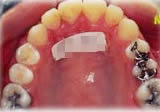

開咬症例

骨格性開咬と診断し、外科的処置を併用して治療。

矯正治療は上下顎歯列を拡大しスペースを作成、非抜歯にて行った。

上顎 上顎 上顎